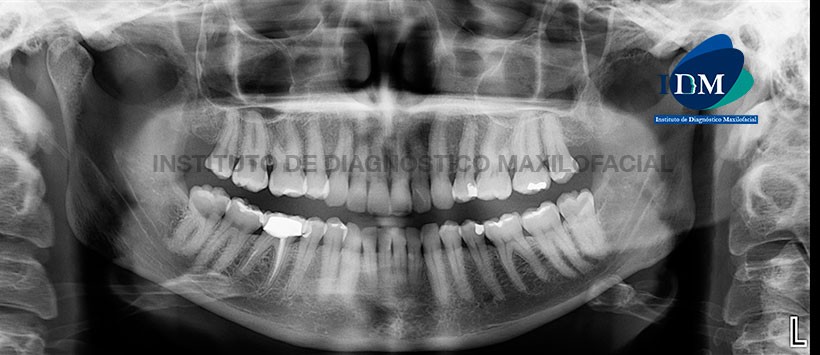

A la evaluación panorámica se evidencian múltiples restauraciones coronarias siendo lo más resaltante el material de obturación de conductos y corona protésica de la pieza 46. Cabe resaltar que en la raíz distal existe material de obturación de conductos de manera parcial. (Figura 1)

En los cortes axiales (Figura 2), transaxiales y tangenciales (Figura 3 y Figura 4) de la tomografía volumétrica de haz cónico se pueden apreciar la presencia de cuatro conductos (dos conductos en la raíz mesial y dos en la distal), los cuales están obturados a excepción del conducto distolingual. Así mismo dicho conducto presenta una obliteración a nivel del tercio inferior en zona apical.

También podemos evidenciar la presencia de un proceso osteolítico de la tabla vestibular a nivel de la raíz mesial de la pieza previamente analizada.